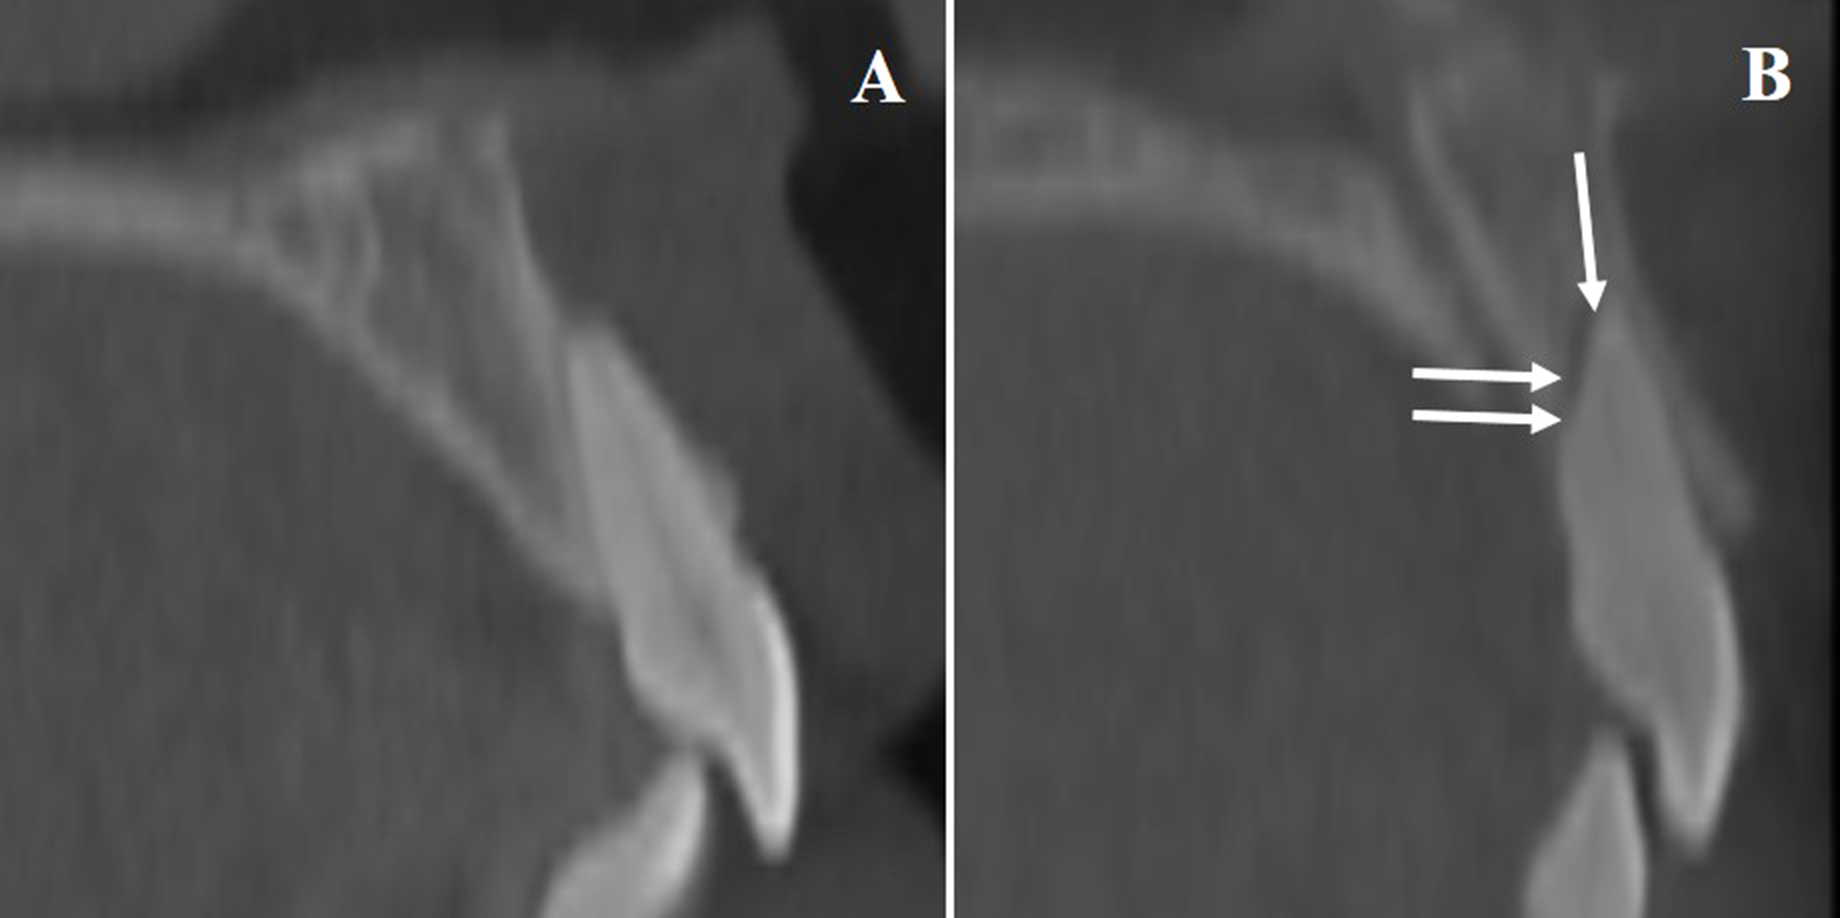

Root resorption was assessed through changes in U1 root length and width, comparing T1 and T2 (Fig. 3). Incisor movement was calculated via CBCT-based cranial base superimposition. Other cephalometric variables recorded included SNA angle, U1-SN angle, and overall treatment duration.

Illustration of Root Resorption in U1. A). Baseline CBCT image of a maxillary central incisor prior to treatment. B). Post-treatment scan revealing evidence of apical and horizontal root resorption (arrows mark the affected zones).